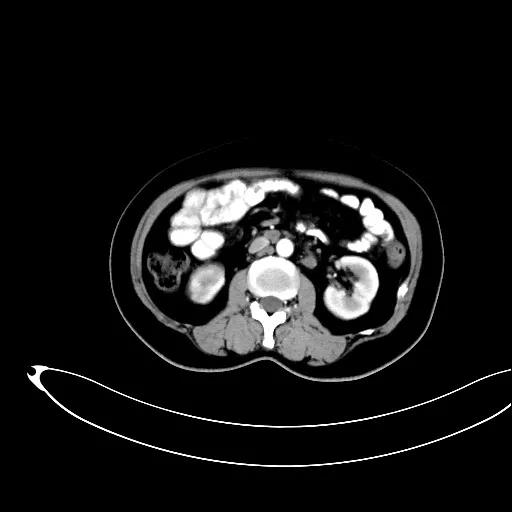

妇科一病区严格遵循指南推荐,在影像学或探查淋巴结阳性的晚期卵巢癌中,若能达到满意减瘤,仍常规行盆腔及腹主动脉旁肿大淋巴结切除/清扫术(如下图举例)。通过前期初步统计分析,肠系膜下动脉至肾静脉下淋巴结转移阳性率为25%左右,在全部腹主动脉旁淋巴结转移患者中约占30%,显示了肾静脉下腹主动脉旁淋巴结清扫的价值。其对生存的影响有待进一步观察。